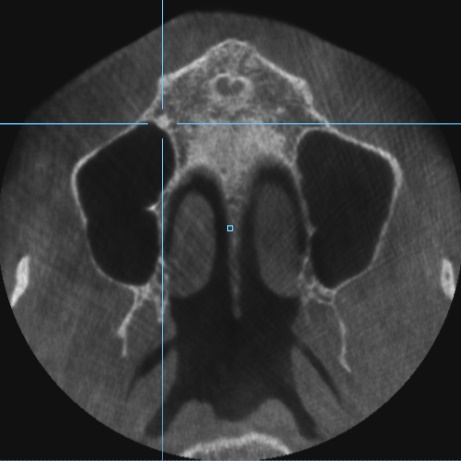

Пропила 2 курса антибиотиков. Хирург сказал, что все зубы в порядке, и отправил домой нервы лечить. Рентгенолог увидела повреждения и сказала не есть больной стороной и вообще не жевать. Это избавило меня от постоянной боли. Но стоит только дотронуться до семёрки, появляется неприятное очущение, как будто он висит на волоске. И в месте удалённой 5 зуд. Как будто кость сломана. Фото с 3д рентгена во время курса антибиотиков.

По этому снимку можно сказать, что немного повреждена передняя стенка, но это не является проблемой. К хирургу обратиться стоит, для того чтобы оценить процесс заживления.